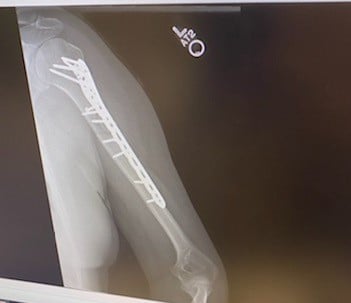

While out jogging one morning in October 2015, I was involved in a hit and run. Emergency Medical Technicians took me to a local hospital where I was diagnosed with a shattered humerus. We decided we only wanted the best care for such a traumatic injury so we got in touch with Esther Shin at Dr. Helfet's office. They could not have been any nicer and accommodating. The entire hospital staff were just amazing from the instant we rolled through the doors through out the entire stay, which was for almost a week. The humerus needed to be put back together with a couple of pins and many screws, as well as the muscle needing to be reconstructed.